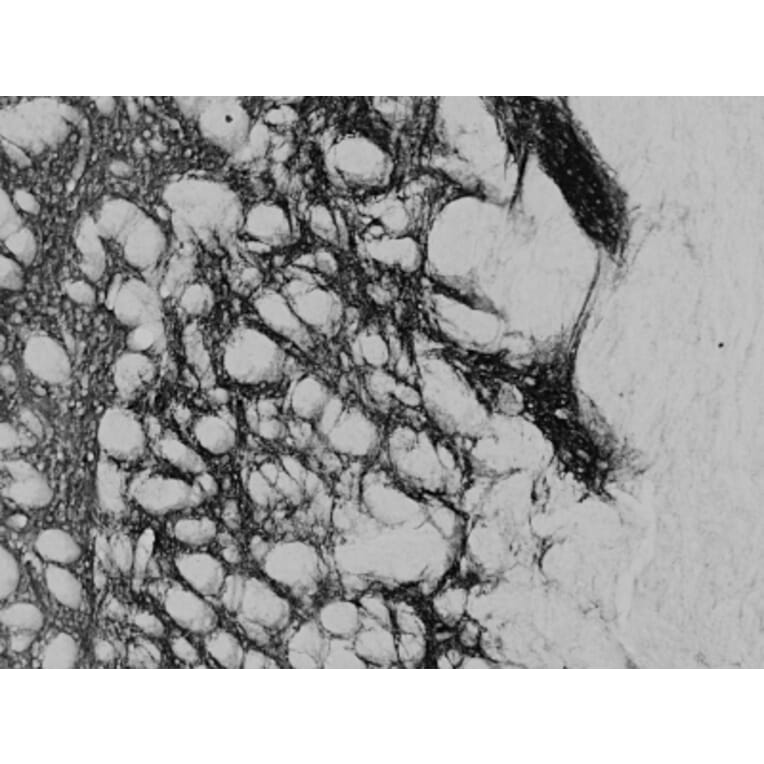

Goat polyclonal antibody to Proenkephalin for ELISA and IHC.

ELISA, IHC

ELISA: 1:32,000, WB: 0.2µg/ml, IHC: 0.02-0.05µg/ml

Mouse, Rat

Synthetic peptide corresponding to the internal region of mouse Proenkephalin.